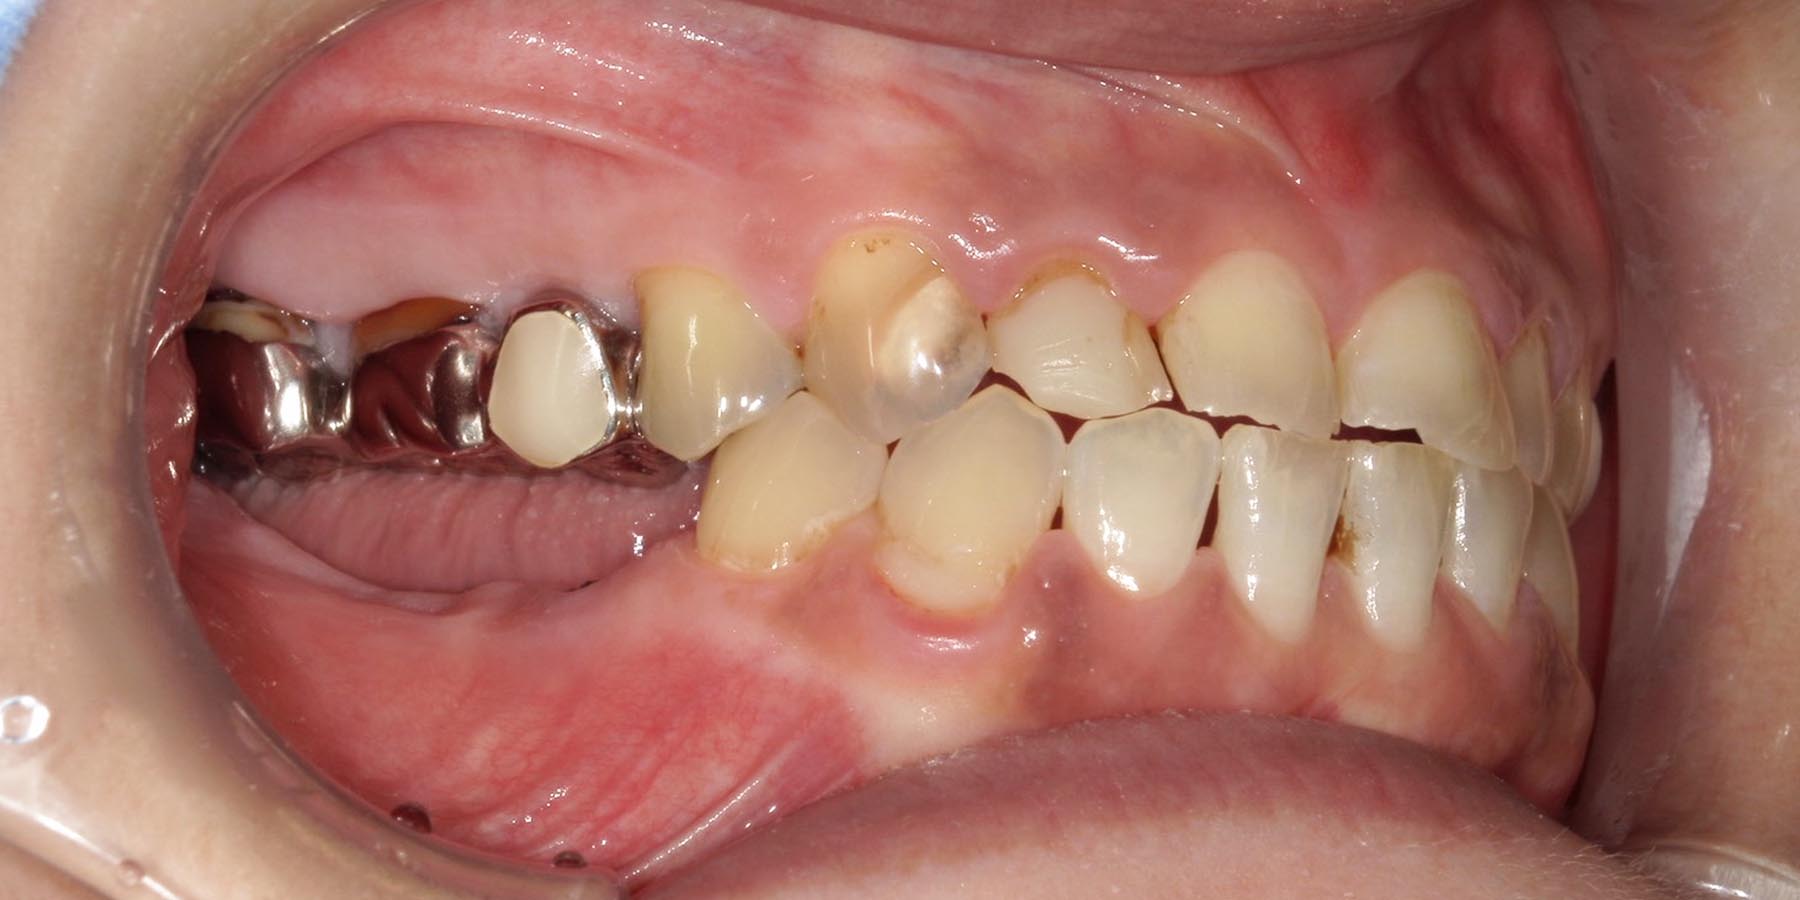

治療前